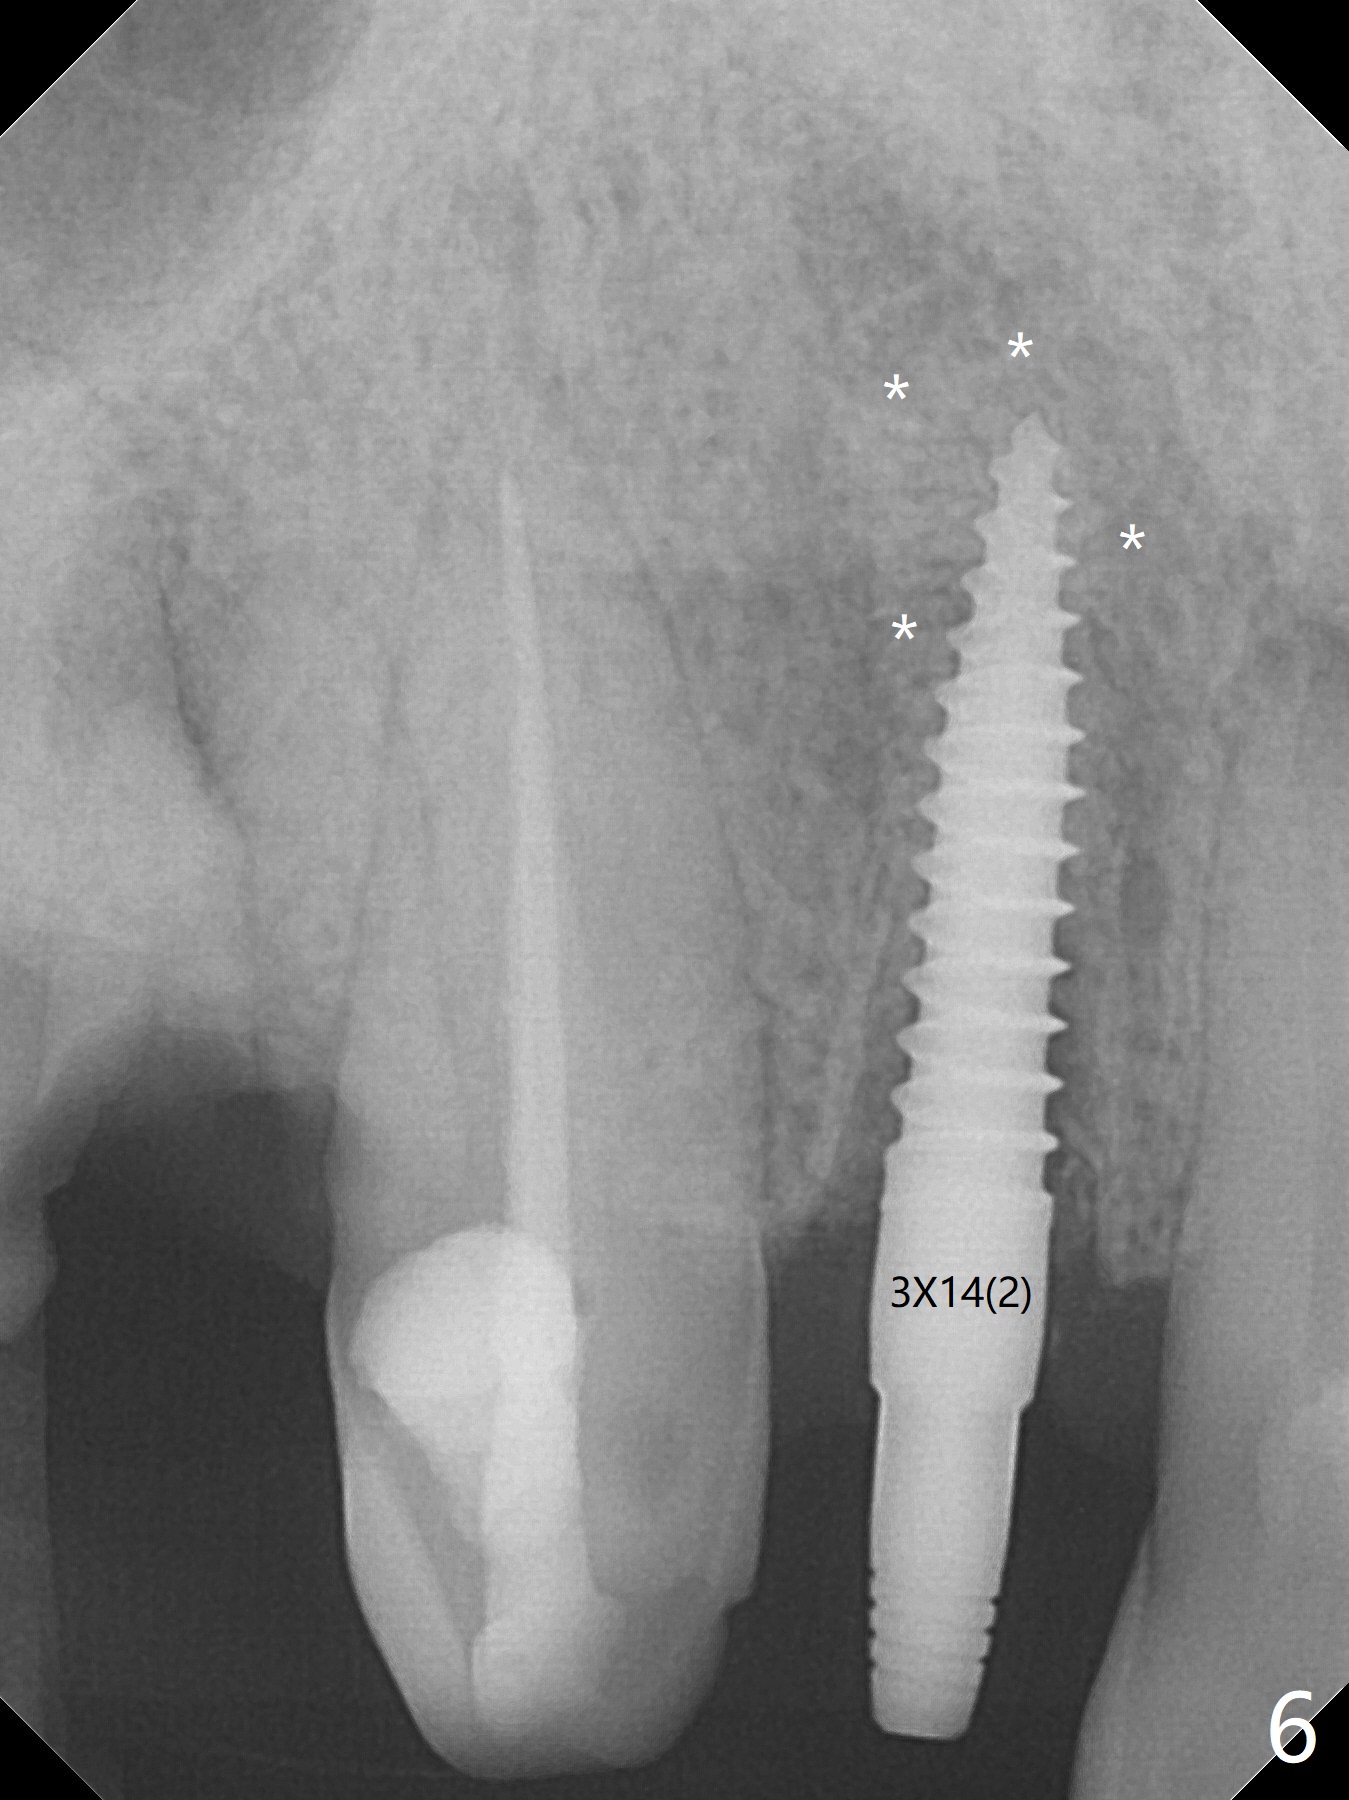

An apical abscess is present when the patient returns for immediate implant at #7 (Fig.1 *); a 2nd challenge is deep bite. After smooth extraction, the apical buccal plate is found to be perforated. Following debridement, a piece of gauze is placed in the apical defect for hemostasis, while osteotomy is initiated palatal (Fig.2). The apical defect seems to be extensive (Fig.3 yellow dashed line). A new trajectory is intended (red arrow) without much success. Before implant placement, bone graft is placed in the apical defect defect area, while a drill (Fig.4 D) is inserted in the finished osteotomy (Fig.5 O). In spite of seemingly large apical defect, the buccal crest bone exists (Fig.4 x). A 3x14(2) mm 1-piece implant is placed with stability; the first round of bone graft is apparently around the apical portion of the implant (Fig.6 *). The coronal end of the implant has to be adjusted several times buccopalatally to accommodate the deep bite. A 2nd round of bone graft following an immediate provisional closes the coronal space of the socket (Fig.7 *). CT will be taken to show the bone graft to repair the buccal plate defect when the patient returns for postop follow-up. In fact the defect is minimal in CT a month ago. The fistula does not disappear 1 week postop, but it is non tender (Fig.8). The patient complains of asymptomatic swelling in the right nostril. CT shows that the large buccal perforation is repaired with large amount of bone graft (Fig.9,10 *). It would be nicer to place the implant slightly more buccal apically (Fig.11 red lines; Fig.12 (preop design)). The buccoapical fistula disappears nearly 1 month postop (Fig.13). The apparently "lifeless" bone graft seems to be harmonious with the surrounding tissue (Fig.14). The periimplant gap reopens with implant mobility nearly 4 months postop (Fig.15), which is related to micro-movement associated with the immediate provisional. The latter is removed. A larger 2-piece implant will be placed in a 2-staged manner if needed (Fig.16). In fact the 3x14 mm straight 1-piece implant (Fig.17) has no mobility when it is retightened, but the trajectory remains buccal. Incision shows that there is no implant thread exposure. A 3x14 mm 15 degree angled 1-piece dummy implant is able to establish the correct trajectory, but there is no occlusal clearance (Fig.18). Micromovement during osteointegration may recreate loosening. Finally using Lindamann bur, the osteotomy is changed so that a 3.5x13 mm 2-piece implant does not need an angled abutment to establish occlusion (Fig.19). There is one palatal thread exposure. Allograft is placed circumferentially, followed by Human Amnion-Chorion Allograft and Collagen Plug. The wound does not heal 8 days postop (Fig.20), as related to the age (79 years old)? The wound appears to heal with a membrane on the surface (Amnion-Chorion one?) 3 weeks postop (Fig.21). The ridge looks wide 3.5 months postop (Fig.22,23). A 4.5x5.5(3) mm appears to be seated incompletely with a gap between the abutment and the implant (Fig.24<). A provisional is fabricated after heavy palatal reduction. Two months later, the provisional fractures. After repositioning the abutment with complete seating and torque (Fig.25), impression is taken. Although the buccal plate is concave, the gingiva remains healthy 10 months post cementation (Fig.26,27).